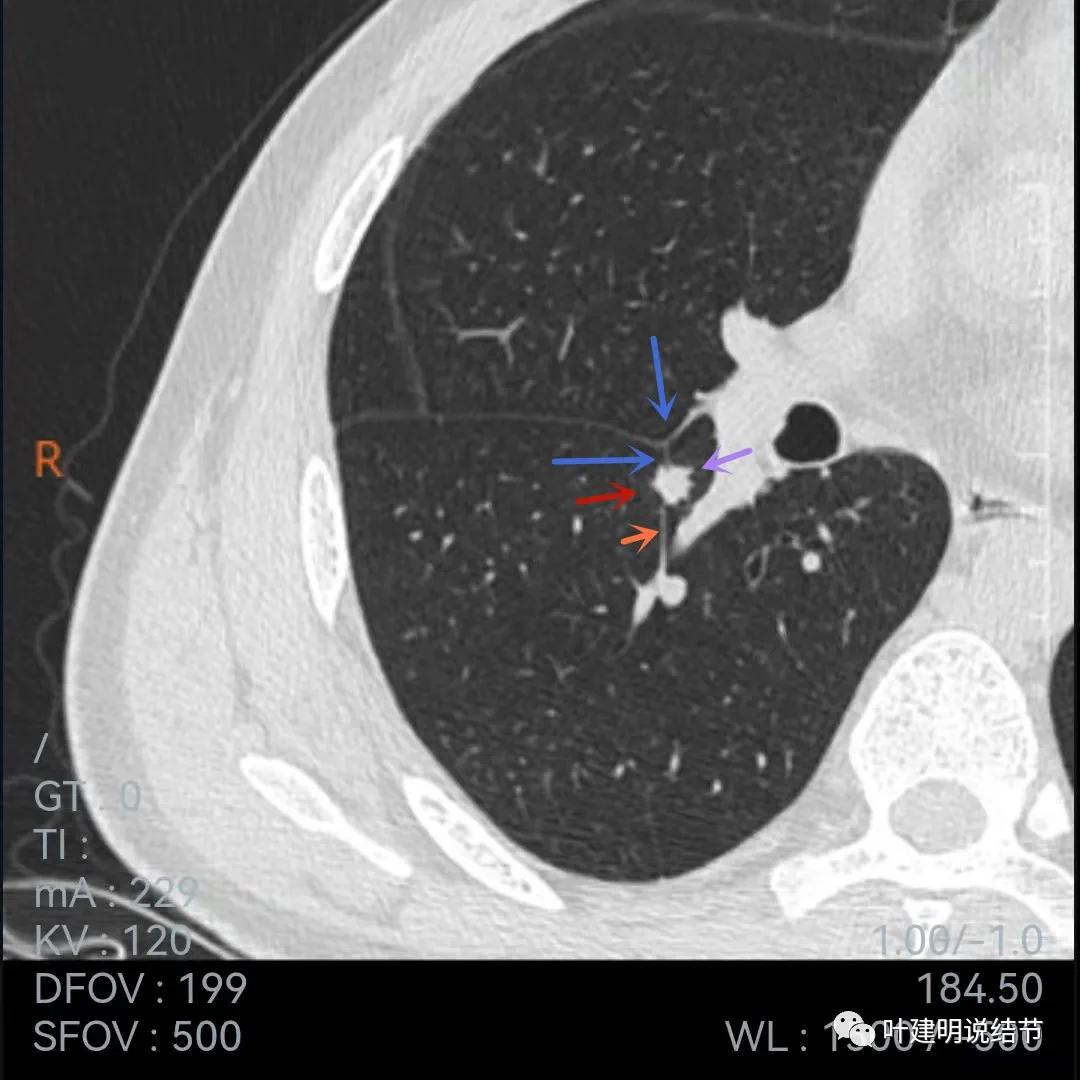

再来看当地医院的靶扫描:

病灶叶间胸膜凹陷,有细毛刺(紫色箭头),但毛刺与病灶大小相比感觉长了点

中间密度还是略低(黄色箭头),胸膜牵拉仍明显(蓝色箭头)

细毛刺(紫色)、胸膜凹陷(蓝色)以及中间偏低密度(黄色)

上图棘突样征象较明显(紫色箭头)

此图不太舒服,胸膜牵拉、表现不平、有微血管征(桔色),但边缘似有少许晕征(绿色),若真是晕征,也是符合肉芽肿性的

上图也示胸膜牵拉、棘突样征,桔色所指似血管进入,但又不太像,增粗的淋巴结管?血管边的是淋巴结吗?不清楚,先不管它

病灶表面不平

病灶密度略不均